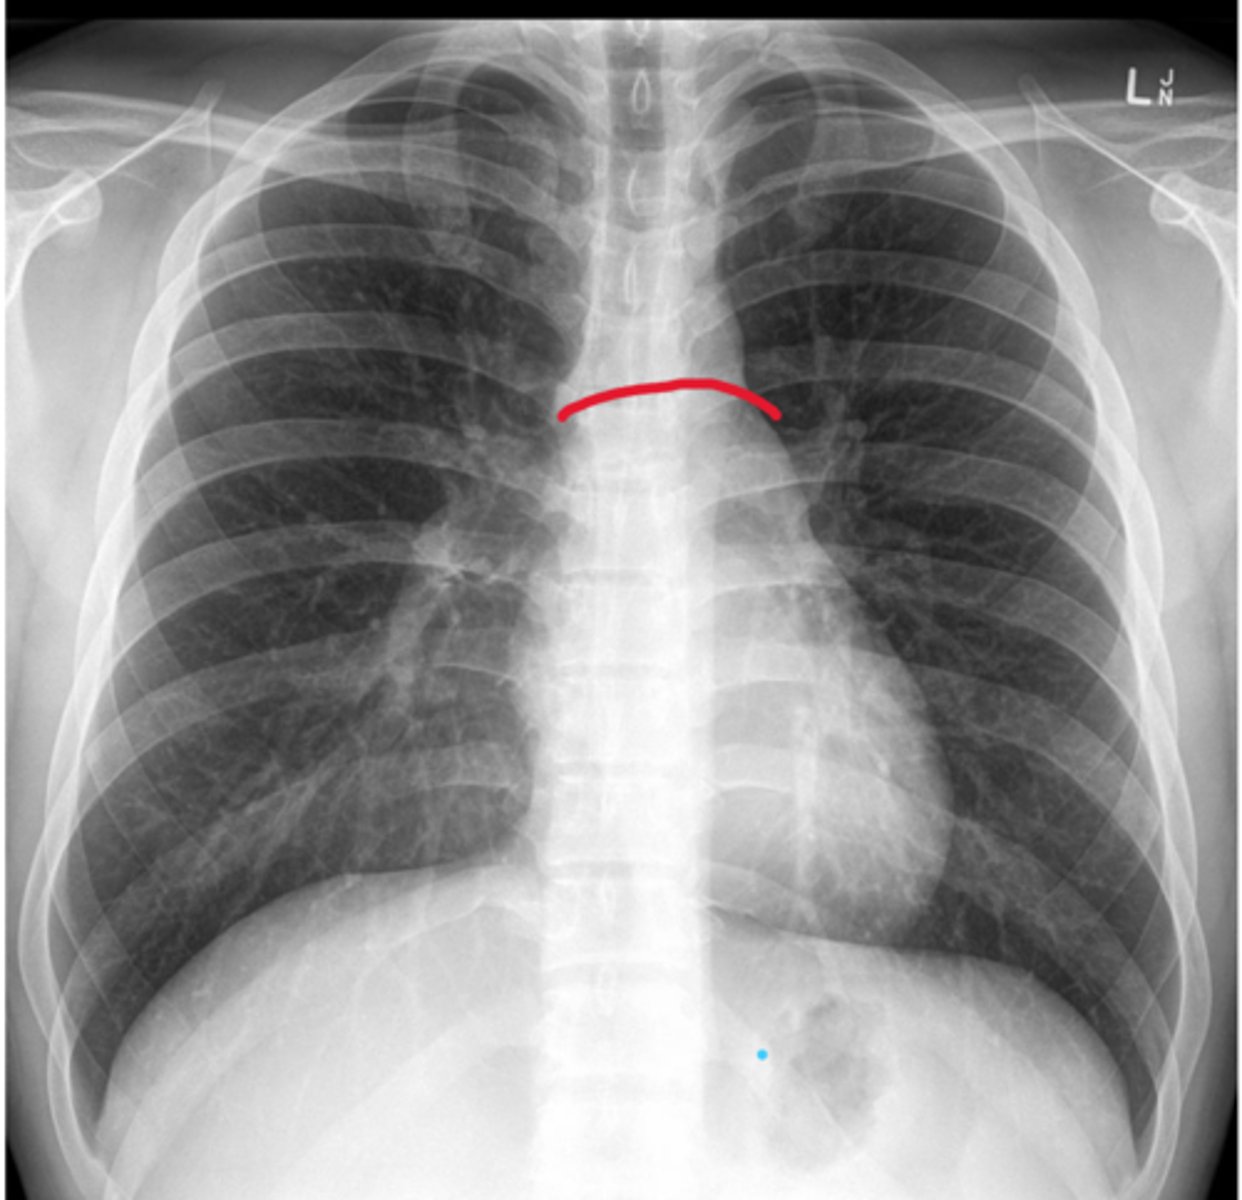

Coronary sulcus

Depression, on top of the heart, inside.